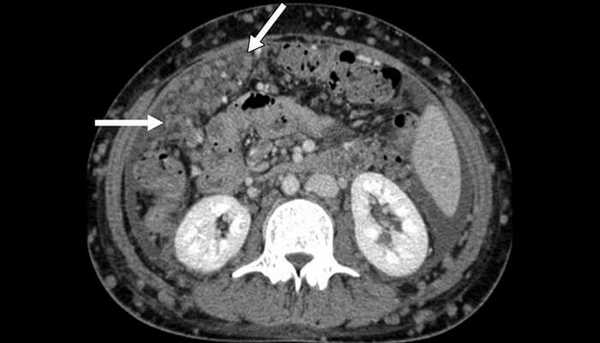

(Слева) КТ с контрастированием, аксиальная проекция: визуализированы несколько отдельных увеличенных лимфатических узлов в парааортальном пространстве (размером 1-1,5 см), характерных для злокачественной лимфаденопатии. Эти метастазы в лимфатических узлах обусловлены раком предстательной железы.

(Справа) КТ с контрастированием, аксиальная проекция: распространенная слившаяся парааортальная лимфаденопатия вследствие метастазирования семиномы. Обратите внимание на то, что аорта смещена от поясничного отдела позвоночника слоем мягких тканей; такую картину не выявляют при типичном ретроперитонеальном фиброзе. (Слева) МРТ, постконтрастное Т1-ВИ в режиме подавления сигнала от жировой ткани: крупное, частично некротизированное забрюшинное образование. Его расположение справа от срединной линии указывает на ипсилатеральную локализацию метастазов по отношению к первичной опухоли в правом яичке.